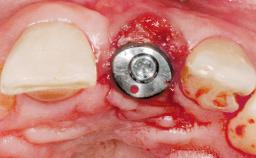

Immediate Placement of an Implant in a Maxillary Left Central Incisor Site

A 33-year-old female patient presented with an upper left central incisor that required extraction after a failed endodontic therapy. The tooth had been traumatized when the patient was a teenager and had undergone several endodontic treatments, including two apicectomy procedures. The patient was in good health and did not smoke. Clinical examination showed that the patient had a high lip line. In full smile, the gingival margins of the upper teeth were visible to the first molars. The gingival margins of central incisors 11 and 21 were only just showing. Examination of tooth 21 confirmed that the tooth was mobile and had hypererupted by 1 mm.

| # of Implants | 1 |

| Type of Implants | One-Piece |

| Attachment | One-Piece |

| Placement Protocol | Immediate implant placement |

| Tooth Site | Maxillary incisor or canine |